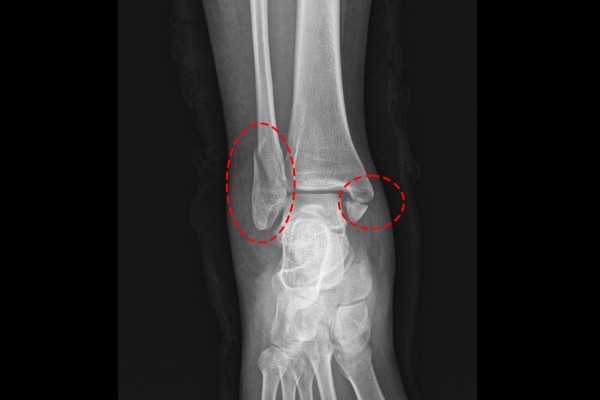

육안으로 보았을 때 발목이 많이 부어 있었고, 지참하신 X-RAY 사진을 보았을 때 안쪽 복숭아뼈(내복사), 바깥쪽 복숭아뼈(외복사)에 골절이 확인되었습니다.

더욱 자세한 확인을 위해, CT 영상을 확인해보니 내/외복사 골절과 함께 뒤쪽 복숭아뼈(후복사)골절까지 확인되며 발목 삼복사 골절(Fx. trimalleolar ankle Rt)을 진단하였습니다.

환자분께 현재 발목 상태와 수술적 치료의 필요성을 설명드렸고, 수술은 발목 삼복사 골절 관혈적 정복술 및 내고정술(ORIF c plate for Fx. Lat malleolar ankle Rt. / ORIF c Tension band wiring Fx. Medial malleolar ankle Rt.)을 진행하기로 하였습니다.